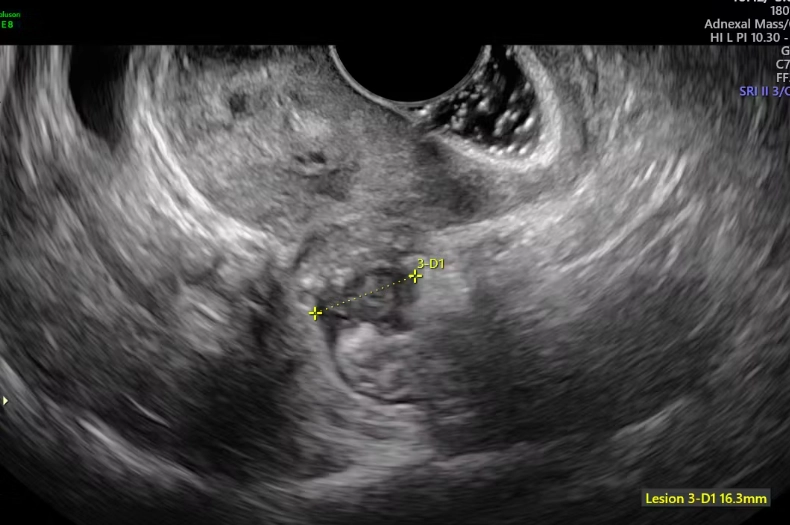

Ultrasound: The First Imaging Step

A transvaginal ultrasound is often the go-to. It's non-invasive and can detect ovarian endometriomas (chocolate cysts) or signs of deep disease. But here's the catch: a normal ultrasound doesn't rule out endometriosis. Superficial lesions are often invisible on ultrasound. According to the American College of Obstetricians and Gynecologists, ultrasound has limited sensitivity for early-stage disease.